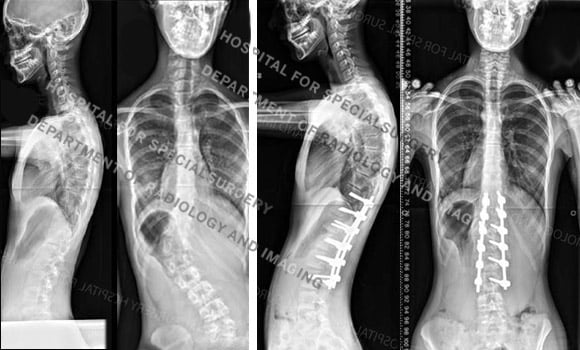

Figure 4. Posteroanterior (back-to-front) Before and after X-rays of the girl in Figure 2a, showing her original spinal curve and correction after fusion surgery.

Mature patients with curves less than 45° are not candidates for spinal fusion surgery since many of these curves will progress slowly or not at all during adult life. Curves measuring greater than 50° are generally managed surgically, since these curves may progress up to one degree per year after maturity is reached. This can present problems for the patient later in adult life.